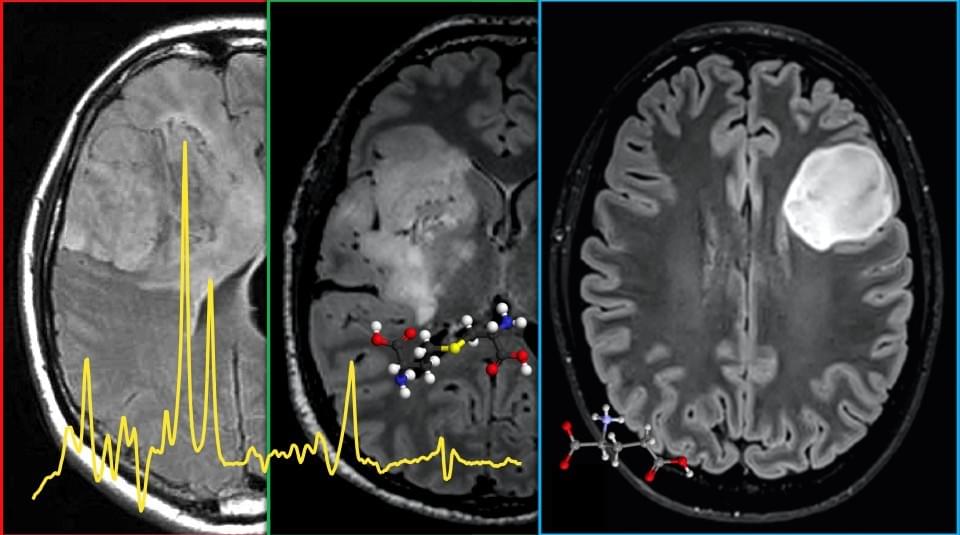

Metabolic alterations are a hallmark of cancer and could represent vulnerable therapeutic targets. In certain tumors, altered metabolism can be caused by peculiar genetic mutations associated with high prognostic value. Notably, noninvasive detection of IDH1/2 mutations in gliomas via D-2-hydroxyglutarate (2HG) quantification, or SDH mutations in endocrine tumors via succinate quantification, significantly help patient stratification and choice of optimal treatment strategies. In this presentation, I will show how tumor subtyping and response to treatment can be predicted noninvasively using advanced in vivo Magnetic Resonance Spectroscopy methods, potentially speeding up the clinical workflow. The role of 2HG in the upcoming IDH-inhibitor treatment era, as well as the clinical potential of recently discovered molecules such as cystathionine will also be discussed.